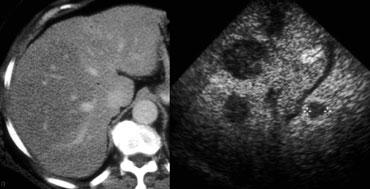

TRÁI: Hình ảnh siêu âm điển hình của u máu. PHẢI: Cũng là u máu nhưng trên nền gan tăng âm, do đó tổn thương tương đối giảm âm. Lưu ý hiện tượng tăng âm phía sau.

Siêu âm

Hầu hết các u máu được phát hiện bằng siêu âm.

Nếu phải chọn một từ để đặc trưng cho u máu trên siêu âm, từ đó có lẽ là ‘tăng âm’.

Tuy nhiên, cần nhận thức rõ rằng điều này đơn giản có nghĩa là tổn thương tăng âm so với nhu mô gan bình thường.

Nếu gan tăng âm do thoái hóa mỡ (steatosis), u máu có thể xuất hiện giảm âm (hình minh họa).

Một đặc điểm quan trọng khác của u máu là hiện tượng tăng âm phía sau.

Điều này là do tổn thương được cấu thành từ các kênh chứa máu.